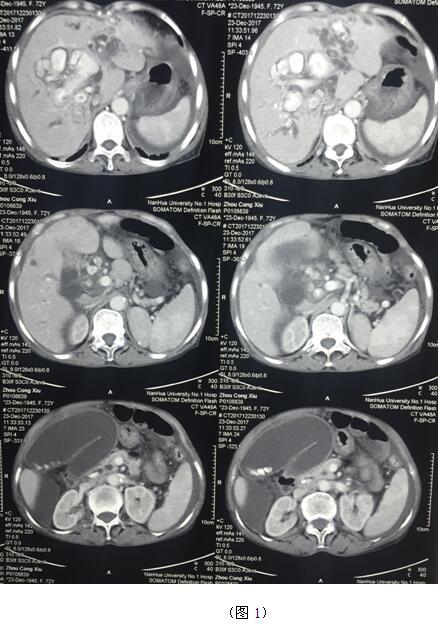

肝膽管結(jié)石疾病往往“鐘愛”貧困落后地區(qū)的病人,70多歲的周奶奶患全肝結(jié)石多年,由于家庭困難一直沒有得到有效治療,這個(gè)月病情惡化出現(xiàn)化膿性膽管炎并肝功能衰竭(圖1)。轉(zhuǎn)輾衡陽市內(nèi)多家醫(yī)院,不是因高昂的治療費(fèi)用止步于院外,就是被以“病入膏肓”為由推脫出院。家屬經(jīng)過多方打聽得知衡陽市中心醫(yī)院是市里面的仁濟(jì)醫(yī)院,肝膽外科還是省級(jí)重點(diǎn)專科,家屬及病人懷著最后的希望來到了醫(yī)院肝膽外科。